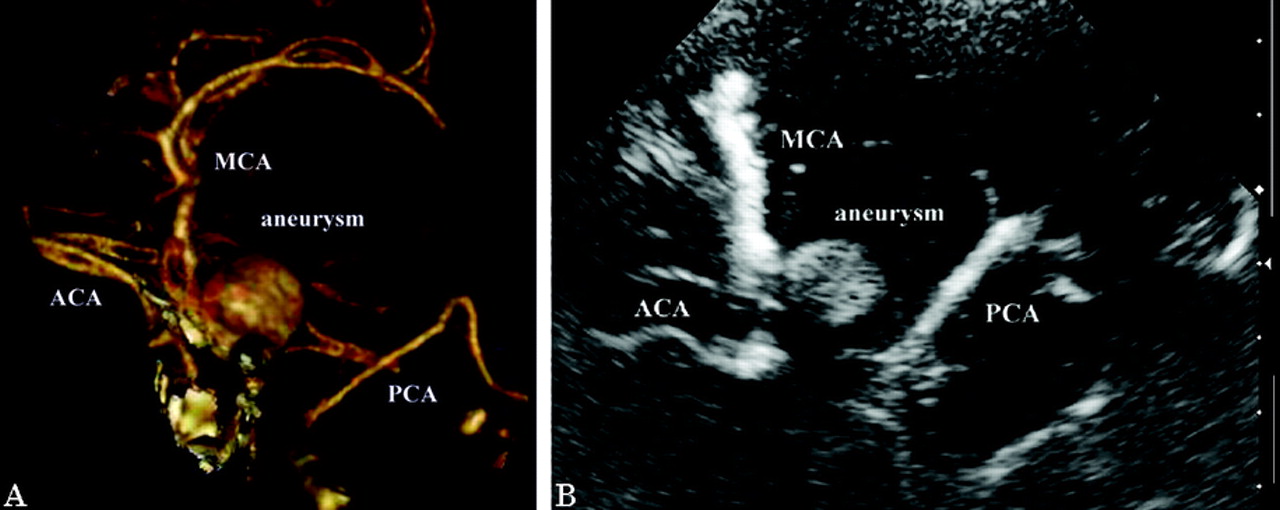

实时流动态的一个巨大动脉瘤